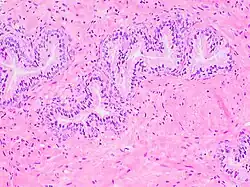

Histology of prostate with gradually increasing simple atrophy from left to right, H&E stain. Crowding and angulation may mimic that of adenocarcinoma, but there is nuclear basophilia rather than atypia, and occasional basal cells can still be seen.